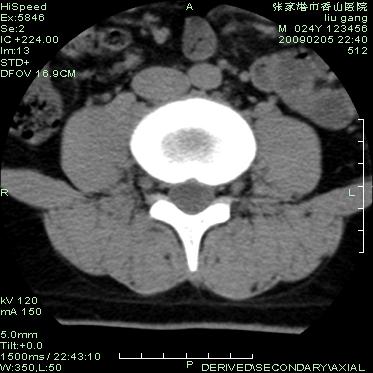

以下是引用随光逐影在2009-3-11 14:43:00的发言:[br]平片:l3、4、5及s1前上缘见类似“切角征”。[br]ct扫描:腰椎多个节段椎间盘向椎体内(椎体前部)突出。